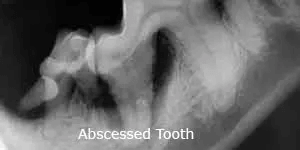

Teeth which feel loose or have pockets will have X-rays to evaluate for bone loss and root abscesses. Our goal is to preserve teeth whenever possible. But, teeth which are loose, abscessed, or have irreversible (Grade 4) periodontal disease will be a continued source of pain and infection. These teeth should usually be extracted to allow the gums and jaw bone to heal.